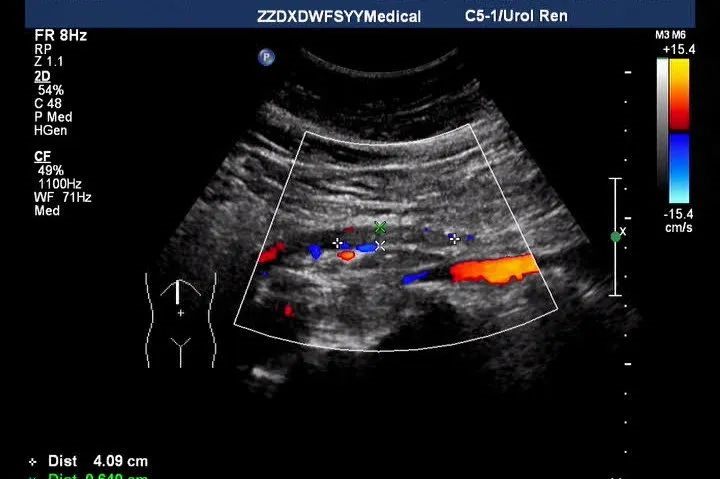

近日,58岁的王女士因腹痛数日就诊于郑州大学五附院,门诊医生开具肝胆胰脾及阑尾区超声检查的申请。超声诊断科程亚南主治医师在为王女士的检查中并未发现明显异常,此时已临近下班时间,患者仍然腹痛难忍,程亚南考虑到可能是相对少见和隐匿的急腹症——肠系膜上动脉栓塞。随即为其进行了肠系膜上动脉彩超检查,发现患者的肠系膜上动脉增宽,且血管内无血流信号,进而明确了之前的判断。

X线、彩超、CTA和动脉造影均可有效检查该疾病。与增强CT和血管造影相比,彩超具有操作简单、安全有效、费用低廉及重复性强的优点。灰阶超声能发现血管管径变化、管腔内有无血栓或斑块,并能简单评估肠壁的缺血程度;彩色超声能直接观察血管内的血流灌注情况,为诊断提供重要依据。